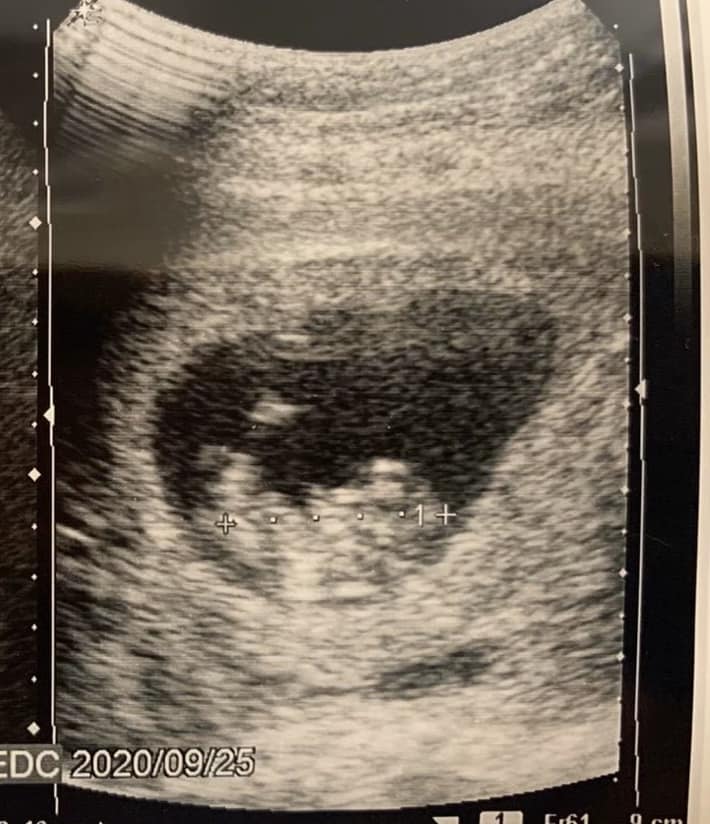

そうなんですよ。ある日、「今日、なるべく早く帰れませんか?」と妻からSNSで連絡が来たんですね。ふだんは気軽なメッセージばかりなのに「帰れませんか?」ってですます調で、何かイヤな予感がして……。「体調が悪いわけじゃないよな?」「離婚したいとかじゃないよな?」とすごく不安になりました。前の妻には「大事な話がしたい」と言われた後に離婚を切り出されたし……、などとあれこれ考えて家に着いたら、腹部エコーの画像を見せられたんです。「妊娠3カ月ですって!」って。

これはもう、うれしかったですねぇ。エコーの画像を二度見、三度見してしまいました。とはいえ、心当たりがない……、と思っていると思い出しましたよ! 年末年始の休みに、ふたりでタイ旅行をしたんですよ。あのときだな、と。